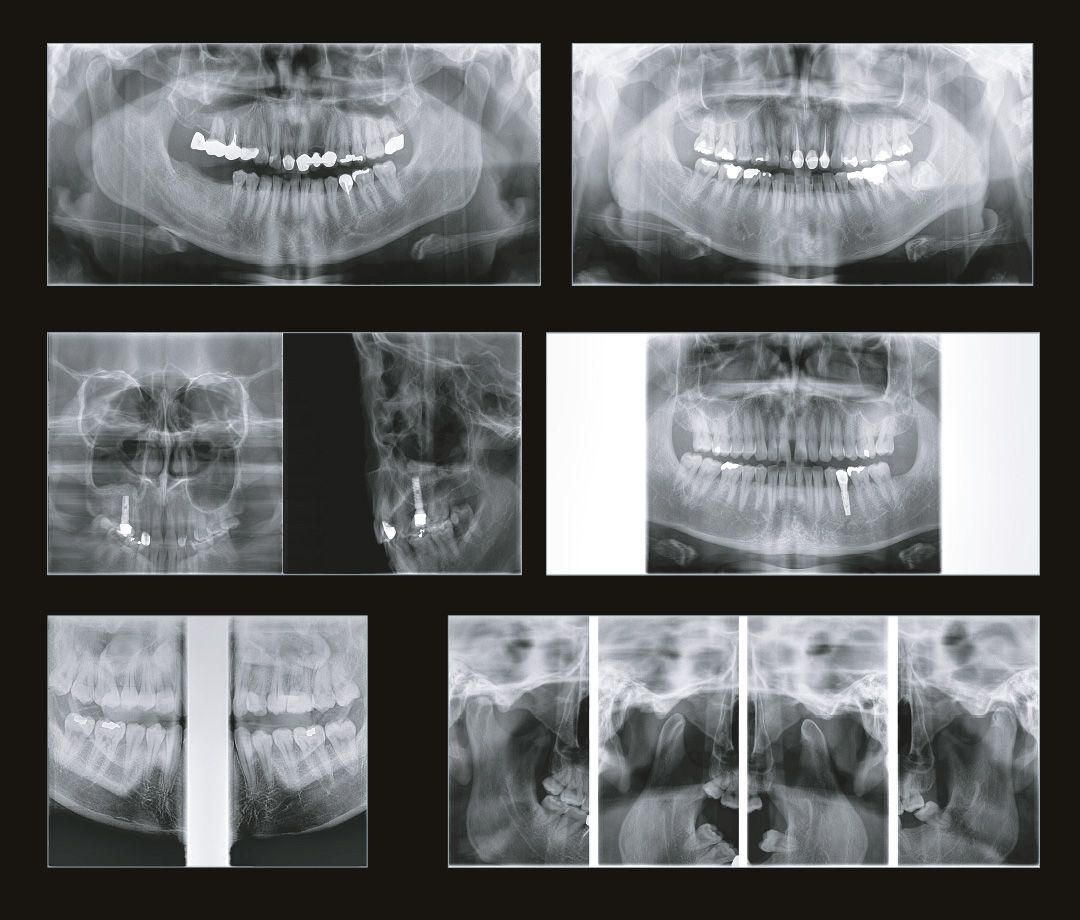

Стоматолог-хирург не способен производить свои манипуляции без снимка КТ, иначе он будет вынужден действовать вслепую, не сумев оценить анатомию области вмешательства.

Стоматолог-ортопед не сможет гарантировать надежность конструкции без правильной оценки стабильности опорных зубов при помощи снимка КТ.

Стоматологу-ортодонту, чтобы правильно простроить план лечения, помимо слепков, так же нужен снимок КТ.